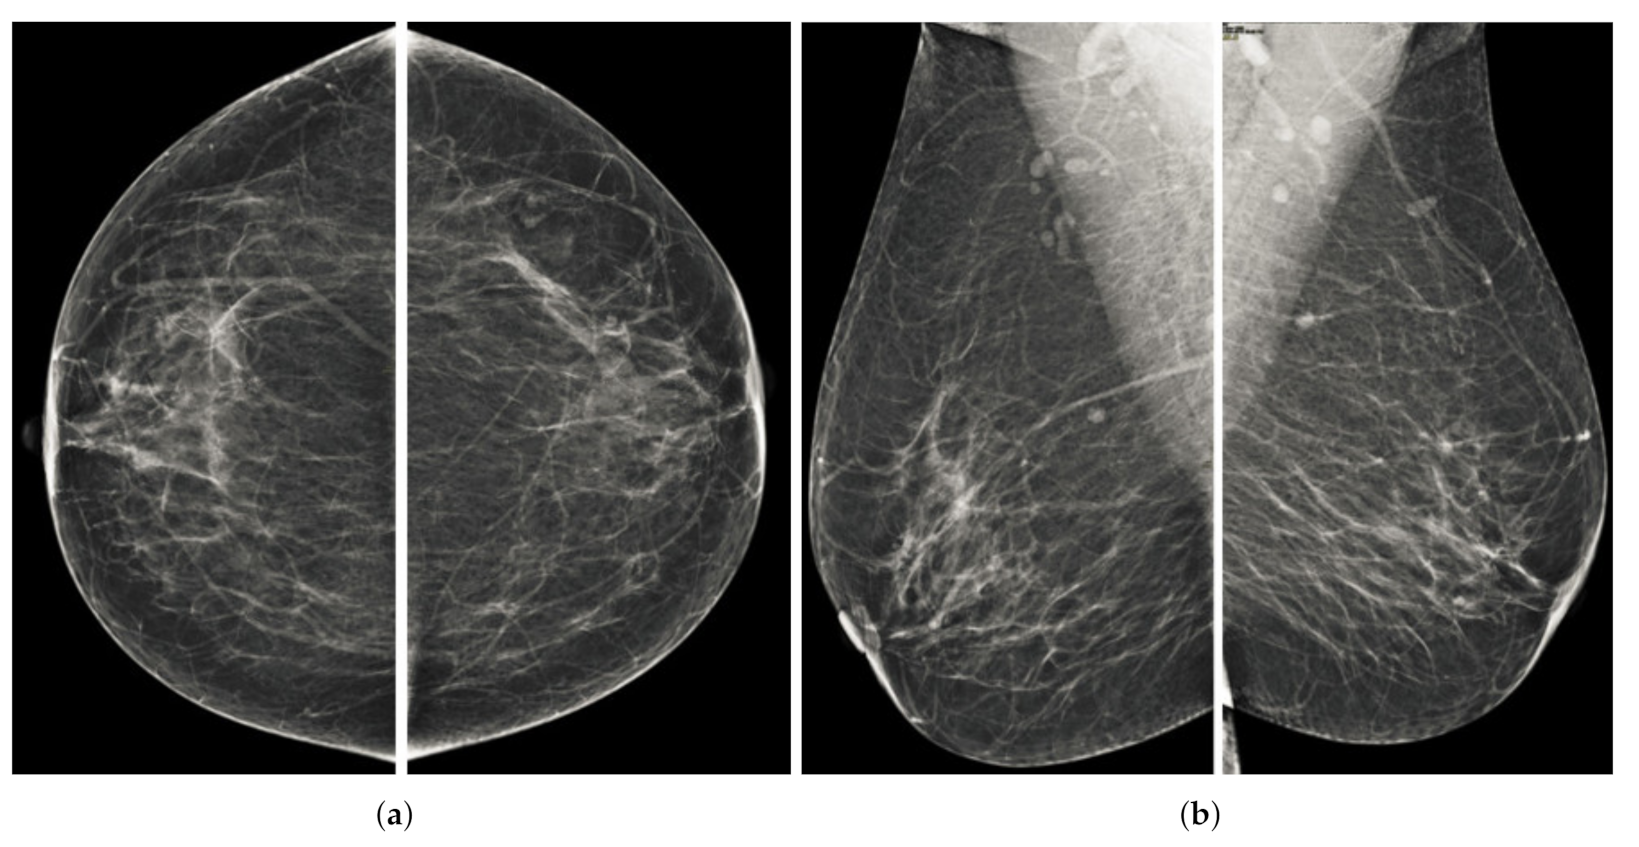

Figure 10.

Analysis of MLO view of BI-RADS-2 mammogram images.